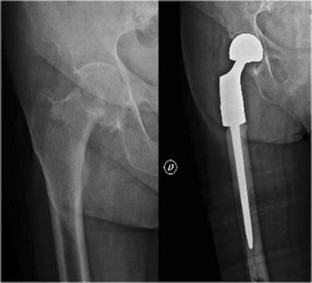

Reconstruction of the proximal femur with a modular resection prosthesis

Various megaprostheses are currently available for reconstruction of the proximal femur after tumor resection. This study evaluates the survival and complications of a modular megaprosthesis for reconstruction of the proximal femur.

We studied the medical files of 109 tumor patients (age range 16–86 years) who underwent proximal femoral reconstruction with the MRP® megaprosthesis from 2002 to 2011. There were 70 patients with metastases, 34 patients with bone sarcomas, and five patients with hematological malignancies; 82 were primary and 27 were revision reconstructions. Mean follow-up was 2.5 years; 31 patients had a minimum five-year follow-up. We evaluated the survival and function of the patients, and the survival and complications of the megaprostheses.

Survival was significantly higher for the patients with bone sarcomas compared to those with metastases and hematological malignancies. Mean MSTS functional score was similar between patients with bone sarcomas and those with hematological malignancies and metastases, and between patients with primary and those with revision reconstructions. Overall survival of the MRP® megaprostheses was 74 % at 5 and 9 years. Fourteen (13.6 %) major complications occurred at a mean period of 1.4 years (range 3 months to 4.5 years); these included infection (5.8 %), dislocation (3.9 %), local recurrence (2.9 %), and acetabular fracture (1 %).

MRP® megaprostheses are a valuable reconstruction option after tumor resection of the proximal femur.

Fig. 1